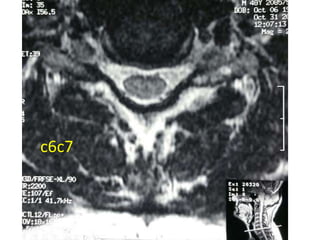

c6c7

48 year old man with right fifth finger pain and numbess